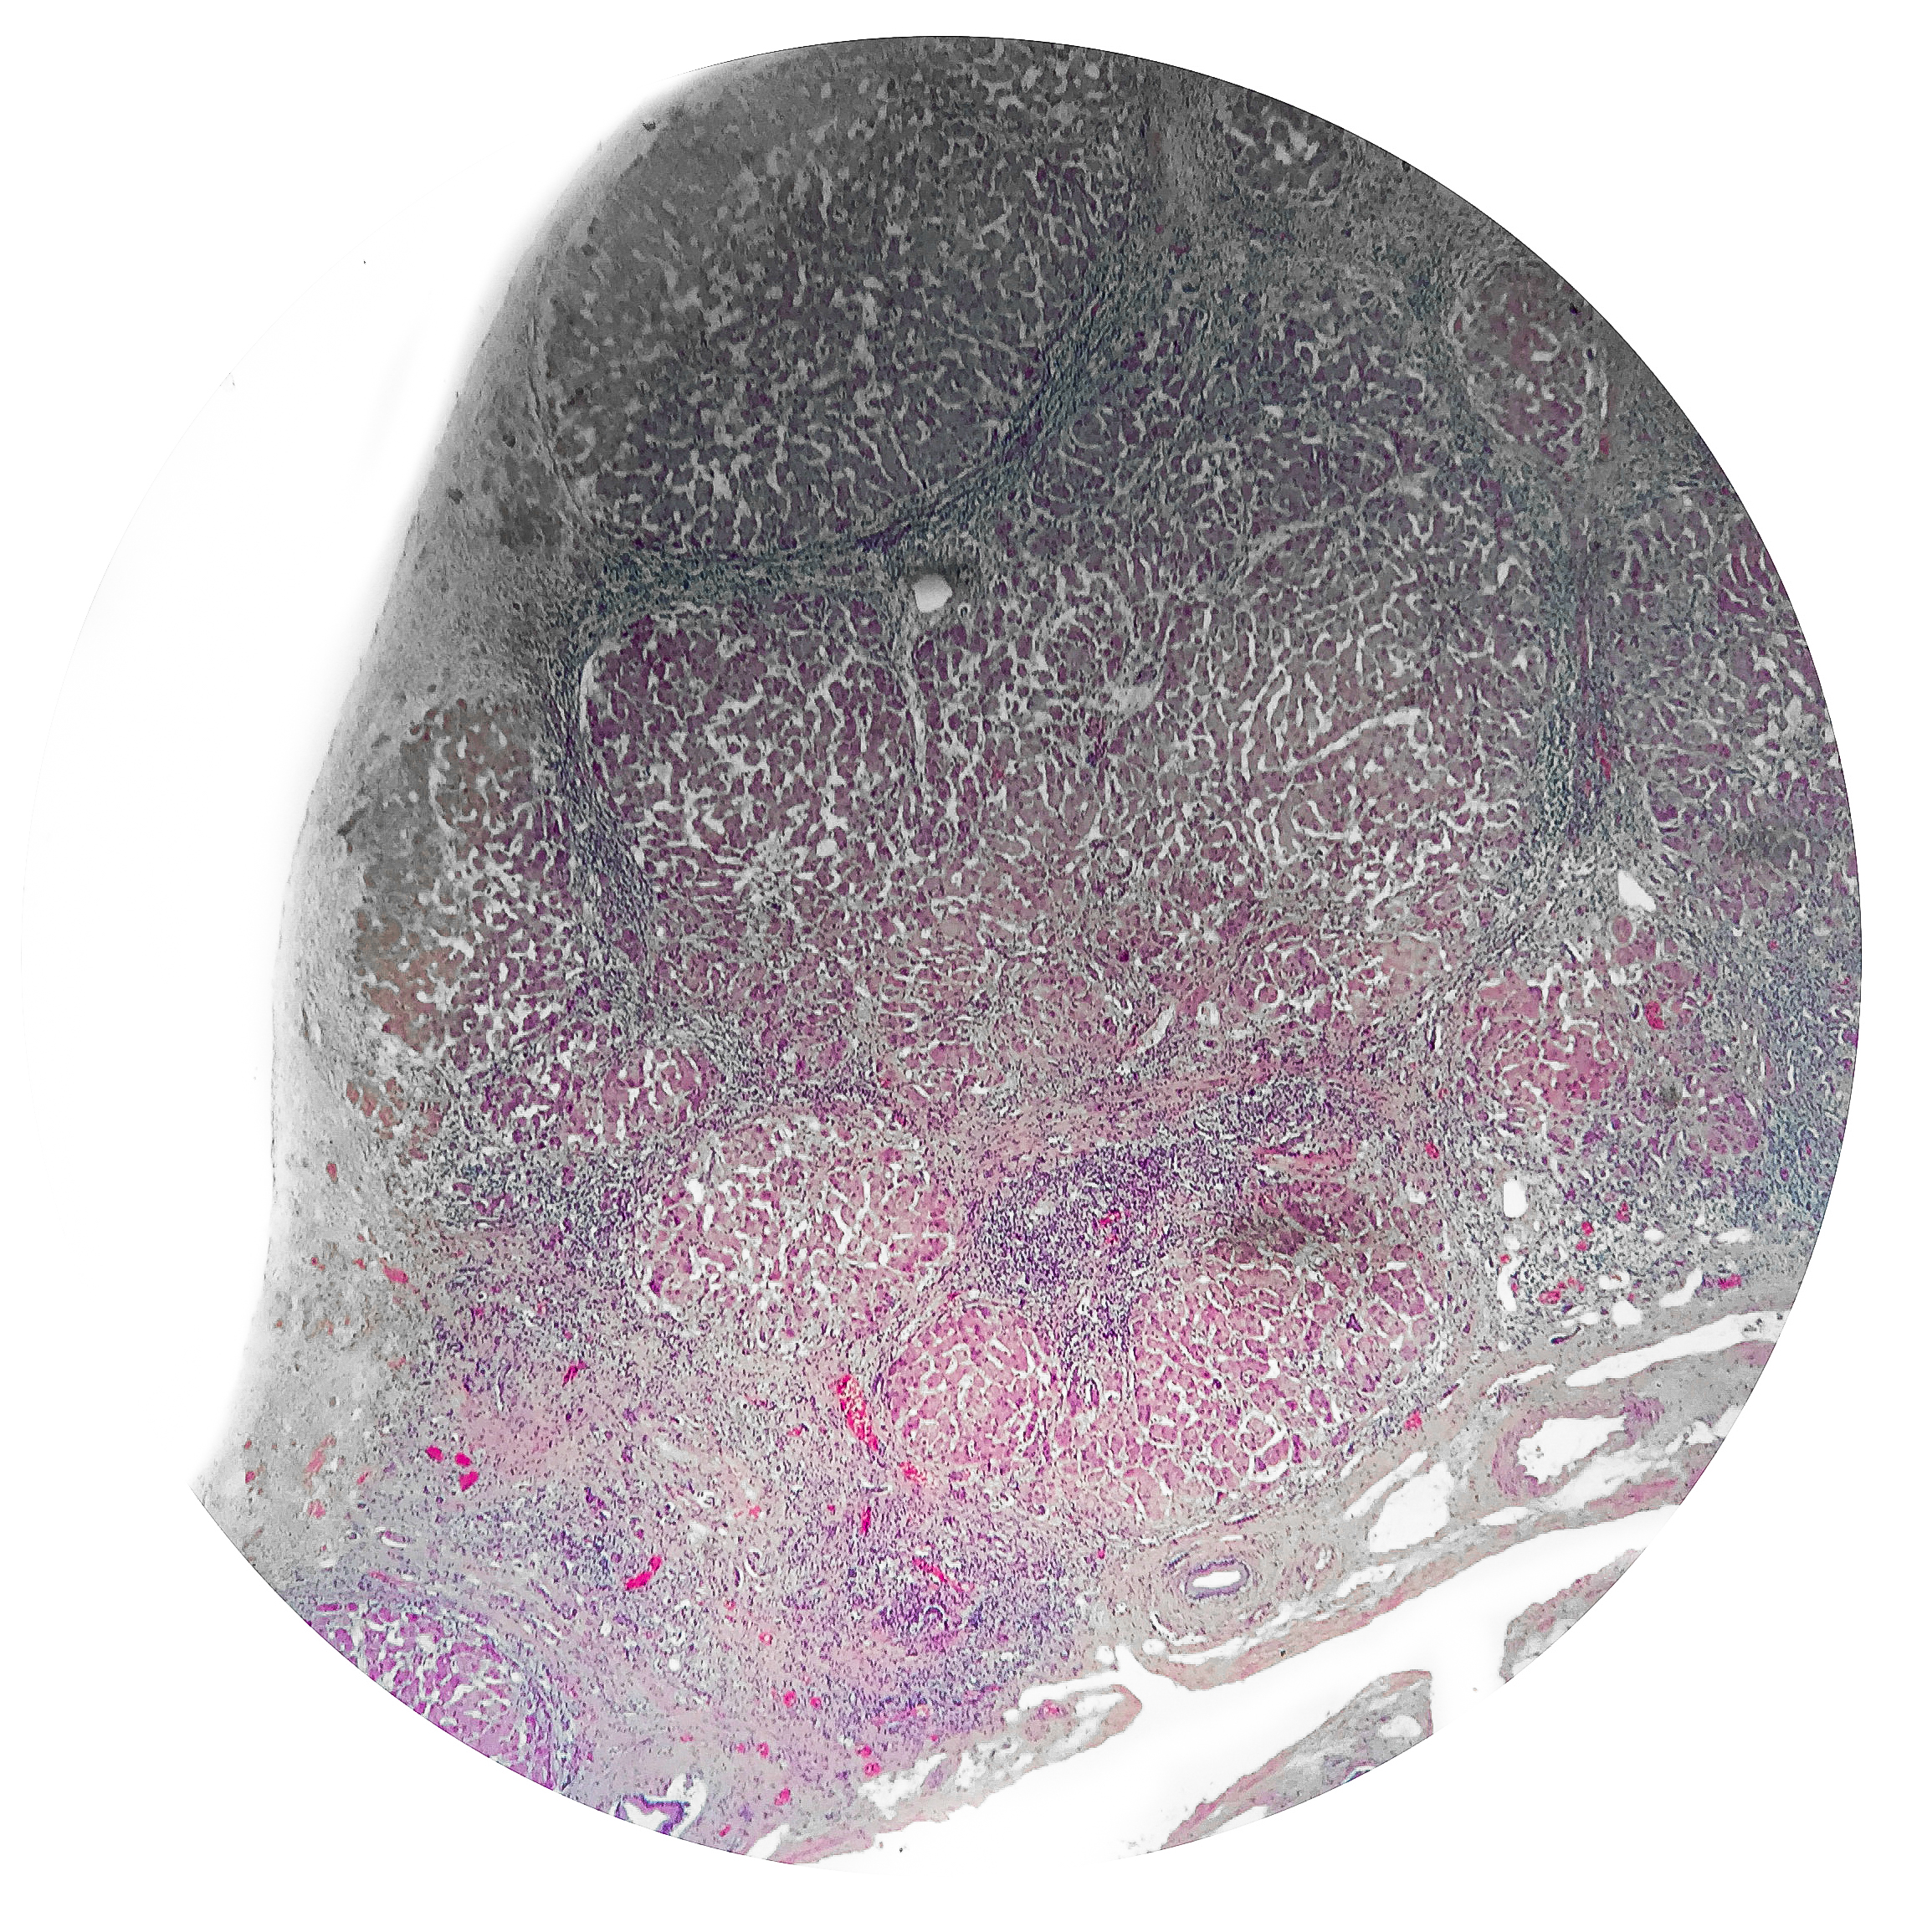

Tuberculosis

Normal State

Diseased State